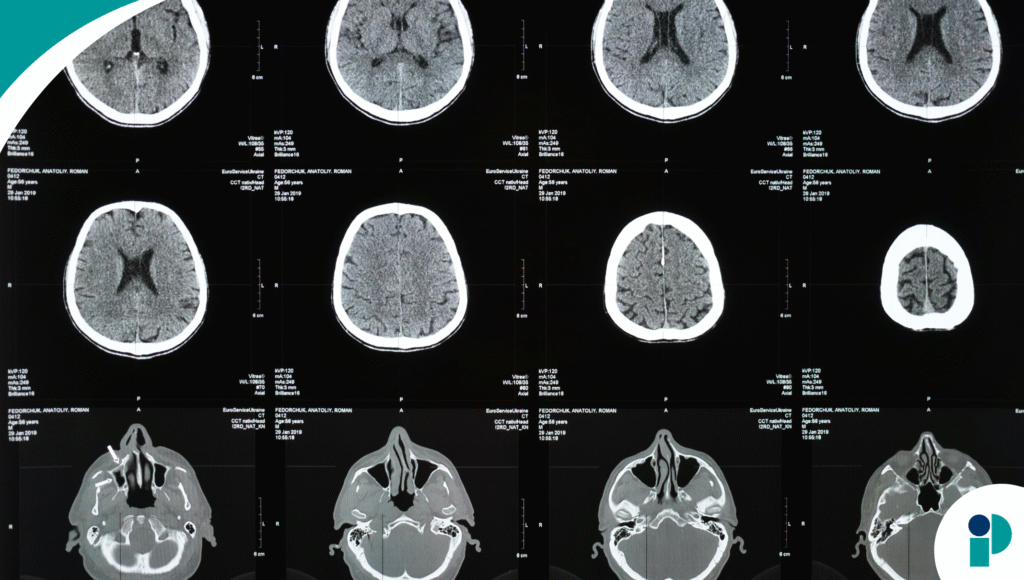

Investigaciones de la Universidad de Bangor y The British Journal of Psychiatry indican que las palabras hostiles repetidas pueden alterar el desarrollo cerebral infantil. La exposición constante al abuso verbal activa de forma crónica las áreas cerebrales relacionadas con la respuesta al estrés, afectando la regulación emocional y la percepción de uno mismo. Esto genera un patrón de hipervigilancia y autocrítica que persiste incluso décadas después.